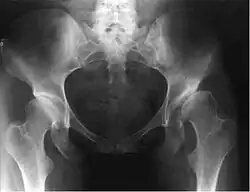

Дисплазия тазобедренного сустава выявляется при рентгенологическом исследовании.

Схема разметки. Линия АВ: нижний контур «фигуры слезы» – наружный край вертлужной впадины (в норме образует угол с горизонтальной осью 40–45°). Линия ВF проведена вертикально вниз от наружного края вертлужной впадины (в норме головка бедренной кости не выступает кнаружи от проведённой линии). Линия CE проведена через центры головки и шейки бедра (в норме проходит через середину отрезка AB, несоответствие свидетельствует о децентрации головки бедренной кости в вертлужной впадине. Линия CD – ось бедренной кости, которая с линией CE образует шеечно-диафизарный угол (в норме угол 120–130°, увеличение угла свидетельствует о coxa valga, уменьшение – о coxa vara).

Наиболее информативным признаком дисплазии вертлужной впадины является угол наклона плоскости входа во впадину (В. Н. Гурьев, 1975), который образуется линиями от края крыши вертлужной впадины до нижнего контура «фигуры слезы» и от нижнего контура последней к горизонтальной плоскости. Увеличение угла свыше 40–45° расценивается как проявление дисплазии тазобедренного сустава. Другим важным показателем является нарушение центрации головки бедренной кости: несоответствие линии, проведённой через центры головки и шейки бедра и линии, через центр вертлужной впадины перпендикулярно линии, соединяющей края вертлужной впадины тазобедренного сустава.